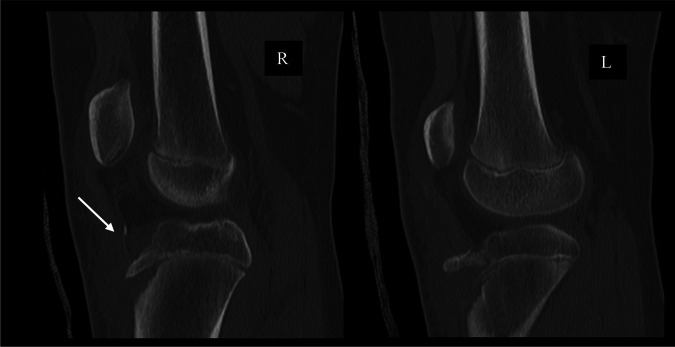

The patient initially presented to the emergency department after a gymnastics injury. She recalled attempting a front flip off a trampoline but landed awkwardly and had immediate pain to both knees. Radiographs obtained in the emergency department revealed bilateral displaced tibial tubercle fractures, as shown in Figure 1. Closer inspection of the radiograph of the right knee revealed an ossific fragment or sleeve fracture of the tibial tubercle. On her physical examination, the patient had tenderness and swelling present about both knees. She was unable to do a straight leg raise for either leg. A CT scan was then performed on both knees, as shown in Figure 2. The patient was later admitted and closely monitored overnight with plans for surgery the next day.

Figure 1.

Radiographs of the right and left knees that reveal bilateral tibial tubercle fractures. The right knee reveals an ossific fragment proximal to the tibial tubercle (arrow).